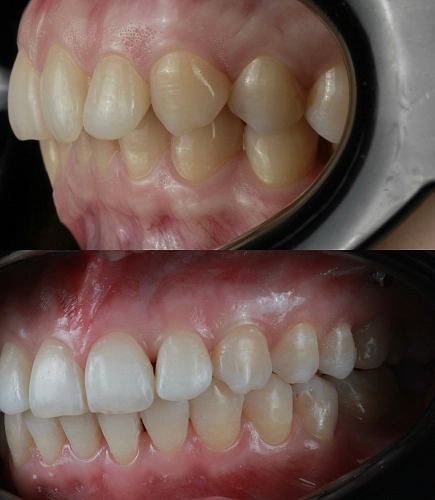

Клинический случай:

Рассмотрим пример ортодонтической коррекции на брекет-системе Damon Q. В данном случае срок лечения составил 1 год и 10 месяцев. За этот период удалось решить несколько важных задач:

• Устранение скученности зубов

• Коррекция наклона верхнего зубного ряда

• Удаление сильно разрушенного зуба на нижней челюсти и закрытие образовавшегося промежутка своими зубами

• Откорректированный прикус и центры зубных рядов

Работа была выполнена врачом-ортодонтом Глуховой Т.А., который тщательно подошел к каждому этапу лечения, чтобы достичь оптимального результата.